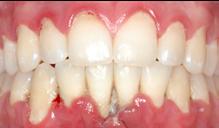

Figure 6.2.a : Parodontite chez un patient de 45 ans. De nombreux dépôts de tartre et de plaque dentaire sont visibles à la surface des dents. La gencive présente une certaine inflammation.

Figure 6.2.b : Sur ce même patient, les lésions osseuses sont visibles radiographiquement avec une perte osseuse horizontale d’environ 20 %.

Figure 6.3.a : Parodontite chez un patient de 25 ans. La gencive n’est pas rétractée et seule une certaine inflammation des tissus est visible, alors que le cas est sévère.

Figure 6.3.b : Les lésions osseuses sont importantes et 80% du support osseux est détruit sur certaines dents.